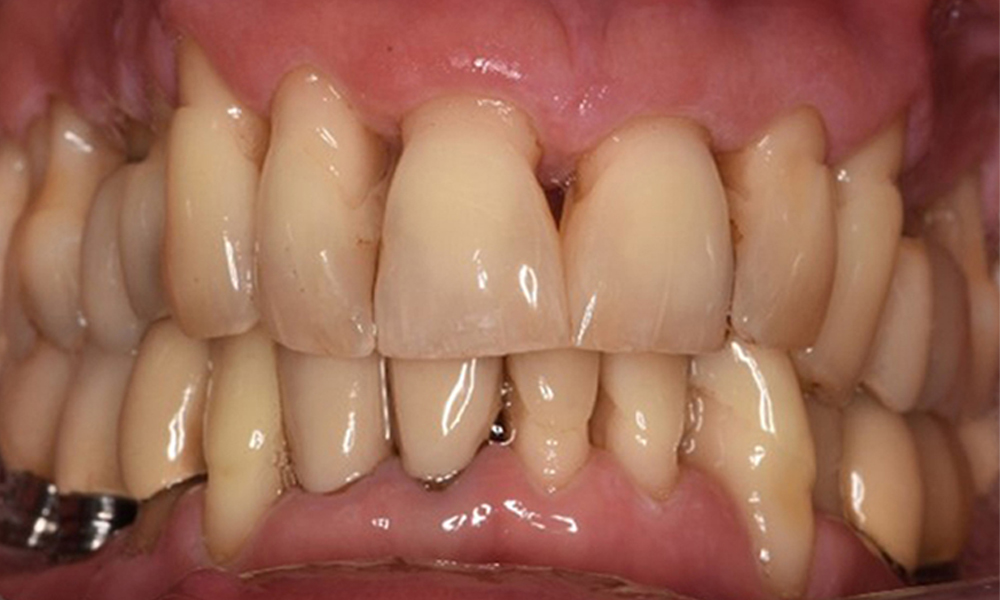

Die Mundhygiene und Mitarbeit des Patienten sind sehr gut (siehe Abbildung "Frontansicht"). Es bedarf lediglich der Reinstruktion und Motivation zum Aufrechterhalten des Mundhygieneverhaltens.